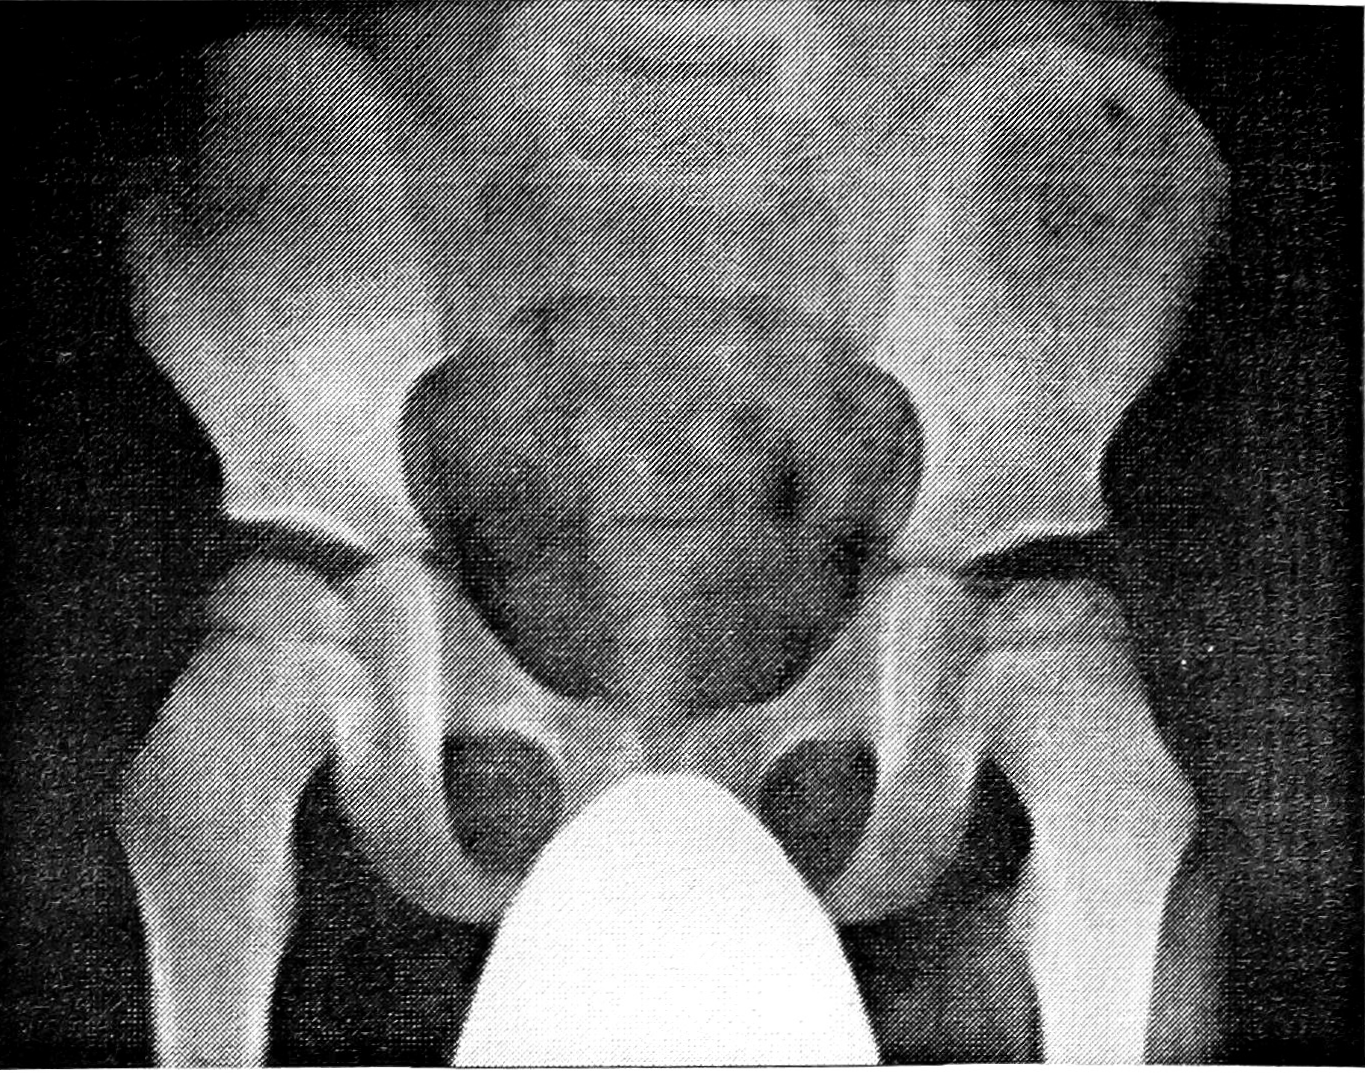

У 8 пациентов, обратившихся с жалобами на боли в тазобедренных суставах, повышенную утомляемость при ходьбе и наблюдавшихся в поликлинике с подозрением на двустороннюю БП, отмечались незначительные изменения в обеих головках бедер: остеопороз, небольшое уплощение, неровность контуров, неравномерность структуры (рис. 3 на вклейке). У 2 больных при наблюдении в течение соответственно 2 и 3 лет заметного изменения рентгенологической картины не обнаружено.

Рис. 3. Больная К. 7 лет. Клинический диагноз: подозрение на двустороннюю болезнь Пертеса.

Головки бедер с обеих сторон уплощены, справа определяется остеопороз, слева — неравномерная структура головки.

При изучении головки бедренной кости (у детей с односторонней БП особое внимание обращали на так называемый «здоровый» сустав) учитывали: наличие остеопороза или остеосклероза, уплощение, характер контуров (гладкие, неровные), структуру (от равномерной до фрагментированной). Типичная картина двустороннего асептического некроза головки бедренной кости выявлена у 11 больных. У 20 пациентов с клиническим диагнозом односторонней БП типичные признаки асептического некроза «здоровой» головки бедра с фрагментацией ее отсутствовали. У 18 из них отмечались: неравномерная структура головки — у 3, незначительное или умеренное уплощение — у 12, остеопороз — у 3, неровные контуры — у 3 (рис. 1 и 2 на вклейке). При динамическом наблюдении на протяжении 2—3 лет эти микросимптомы на «здоровой» стороне у 2 больных развились в типичную картину асептического некроза головки бедренной кости. Лишь у 2 из 20 пациентов изменения выявлялись только с одной стороны: у одного ребенка (12 лет) была типичная картина односторонней БП, у другого (5 лет) изменения ограничивались неравномерностью структуры и неровностью контуров головки бедра.